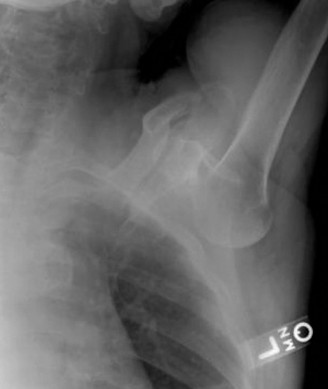

A sophomore, high school wide receiver presents to your clinic at the beginning of his football season. He reports a dislocation event after being tackled; his shoulder was “put back in place” by the on-field athletic trainer. A CT scan taken in the hospital today is shown (Fig. 2–33). He has been recruited by numerous colleges, plans to play at a division 1 school, and is very eager to return to the field.

Figure 2–33

The correct answer is (E). A large bony fragment (>20%) makes the failure rate with nonoperative treatment (Answers A, B) unacceptably high. This question is meant to illustrate the challenges associated with treating an in-season athlete and highlighting the indications for surgery after a first time dislocation event. Typically, early in a season, providers will initiate an aggressive PT program and try and return athletes to the field within a few weeks so that they can play out the remainder of the season. Towards the end of the season, when there is insufficient time to rehab a patient, one may choose early surgery so that the patient has maximal time to recover prior to the next season. In this case, even though the

patient is extremely motivated to return to the field and has only sustained a single dislocation event, the large bony Bankart lesion behooves surgical treatment. The best option for him would be to have early surgery and have a maximal amount of time to prepare for his senior season. A Latarjet procedure (Answer C) is used for patients with recurrent anterior instability and significant glenoid bone loss, and the Magnuson–Stack procedure (Answer D) is a largely historic procedure that was used for recurrent anterior instability. Objectives: Did you learn...? The common presentation of a patient with shoulder instability?